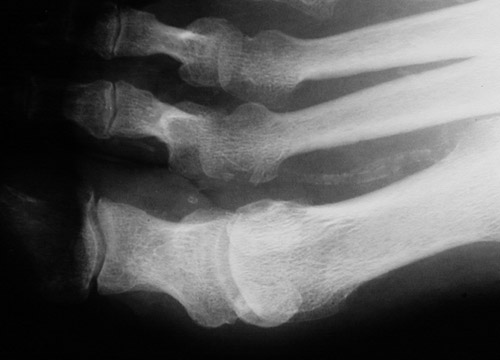

| Here is a case of osteomyelitis involving the great toe of the foot. Note the sclerosis with adjacent rarefaction of bone. This condition can be difficult to treat, since bone is not highly vascular, so high antibiotic concentrations can be difficult to attain. A closer view of this process is shown below. |